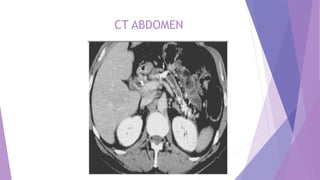

Currently, CT is regarded as the

imaging modality of choice for the

initial evaluation of suggested

chronic pancreatitis.

The diagnostic features of:

• pancreatic ductal dilatation (68%)

• parenchymal atrophy (54%),

• pancreatic calcifications(50%)

• pancreatic enlargement

• thickening of the peripancreatic

fascia, and

• bile duct involvement

are depicted well on CT scans.

CT Findings

CT ABDOMEN